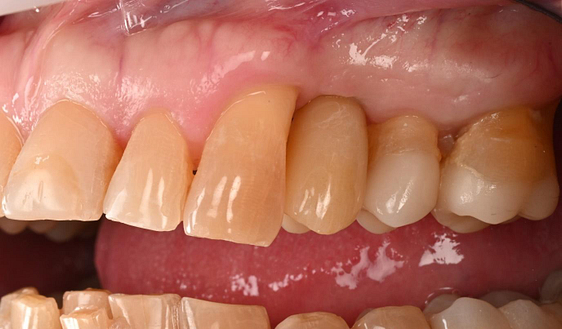

The crown was milled from a high-strength, multilayered zirconia and hand-finished to achieve a lifelike appearance.

At the final appointment, the crown was securely attached to the implant, resulting in a beautiful, natural-looking restoration.

The implant-supported crown seamlessly integrated with the patient's natural dentition, and the patient reported excellent comfort and function.